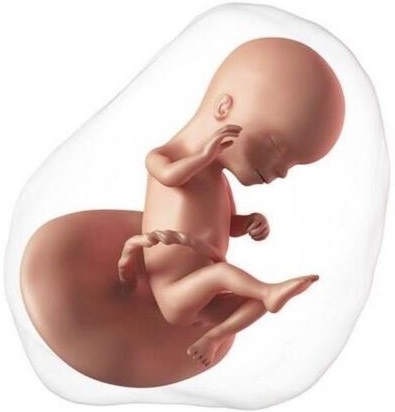

El embrión ya tiene forma de un pequeño cuerpo humano, mide aproximadamente 20 mm de cabeza a pies. En la cara se forman estructuras pequeñas como la retina y los párpados, el labio superior, la nariz y las orejas.

El cuerpo se va alargando, en las extremidades tiene unos surcos que darán lugar a los dedos. El embrión empieza a moverse, son los primeros movimientos involuntarios del embrión.

El embrión se alimenta de la vesícula vitelina, un pequeño anillo que se observa al lado del embrión cargado de nutrientes, pero ahora necesita mucho más oxígeno y alimento, tiene que usar la placenta.

En estas semanas ya se ha formado el cordón umbilical cuya función es llevar sangre hasta la placenta y devolverla al bebé; ahora empezará a depender de la placenta. Ésta última le proporciona oxígeno, nutrientes y agua, y elimina los desechos del metabolismo. Es importante recordar que las sustancias nocivas para el embrión como el tabaco, las drogas, los químicos o el alcohol también atraviesan la placenta.